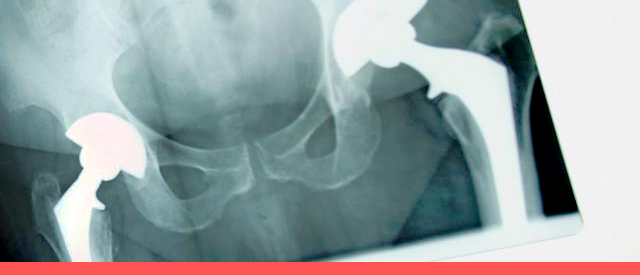

晚期患者关节强直,除了脊柱活动度消失,无法活动颈部、弯腰、扭腰以外,最严重的问题就是髋关节强直。关节一旦出现强直,药物治疗手段将回天无力,只有通过外科介入才能改善。外科治疗的时机是:内科治疗无效,合并关节功能障碍或畸形,日常生活受到影响。

近年来,人工全髋关节置换术的出现,为合并髋关节强直的患者带来了福音。人工关节置换术可切除骨性融合的股骨头和髋臼,转而在原髋臼的位置重头置入人工髋臼,同时,在股骨上段重头置入股骨柄和股骨头人工关节假体,从而再造髋关节,恢复髋关节的活动功能。通过人工全髋关节置换,可以重头赋予患者正常的行走功能,给晚期的强直性脊柱炎患者创造崭新的生活。